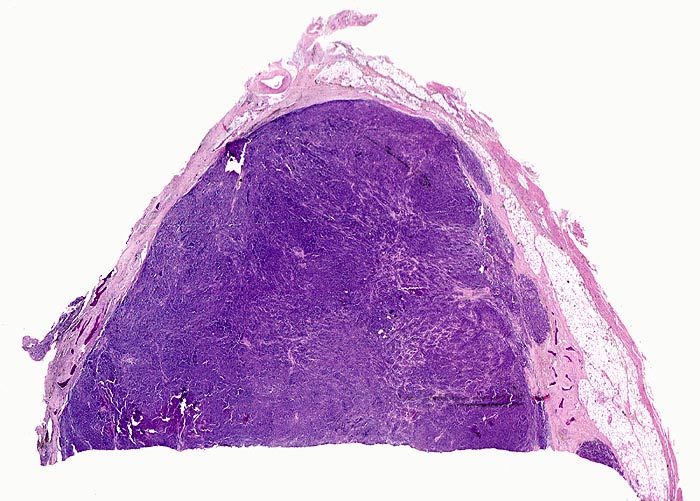

Knochenmarkstanze mit nodulärer Hyperzellularität des blutbildenden Marks.

Keine wesentliche Osteopenie.

In den hyperzellulären Arealen dichte Rasen neoplastischer atypischer Plasmazellen.

Ausserhalb der Plasmazellrasen findet sich spärlich residuelles blutbildendes Knochenmark.